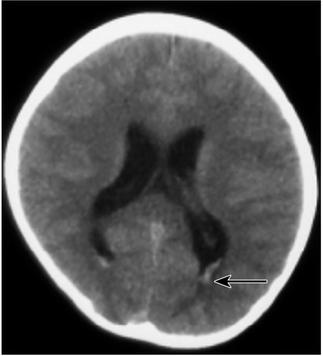

患儿,女,10岁,因“3个月内抽搐2次”于2010年10月23日入本院儿内科。患儿于入院前3个月(2010年7月21日),无明显诱因出现头痛,头痛后出现抽搐,抽搐表现为意识丧失、双眼紧闭、头后仰、全身僵直、双手握拳屈曲、小便失禁,持续约1~2分钟后自行缓解,缓解后意识清楚、全身发软,伴呕吐数次,为非喷射性,呕吐物为胃内容物,发病1天后出现头痛、腰背部疼痛,不伴有发热、腹泻。就诊于当地医院,查颅脑MRI及MRA未见明显异常,行腰椎穿刺术未成功,给予地塞米松及其他药物(具体不详)治疗后好转,未再出现抽搐及头痛。本次入院前3天(2010年10月20日)患儿诉咽痛,无发热、呕吐、腹泻,自服小儿氨酚烷胺颗粒治疗,于当日夜间再次出现抽搐,表现同前,抽搐后亦出现头痛、呕吐及颈项强直,就诊于某市级儿童医院,查颅脑CT检查(图1),显示“脑室系统饱满,双侧脑室后角室管膜下血管影显著,余颅脑平扫未见异常”;血常规、血生化及血气分析检查均未见明显异常。给予头孢甲肟、甘露醇、布洛芬等治疗,仍有间断头痛,为求进一步诊治就诊于本院,门诊以“抽搐原因待查”收入院。

图1 首次颅脑CT检查(外院,2010年10月20日):脑室系统饱满,双侧脑室后角室管膜下血管影显著(箭头),余颅脑平扫未见异常